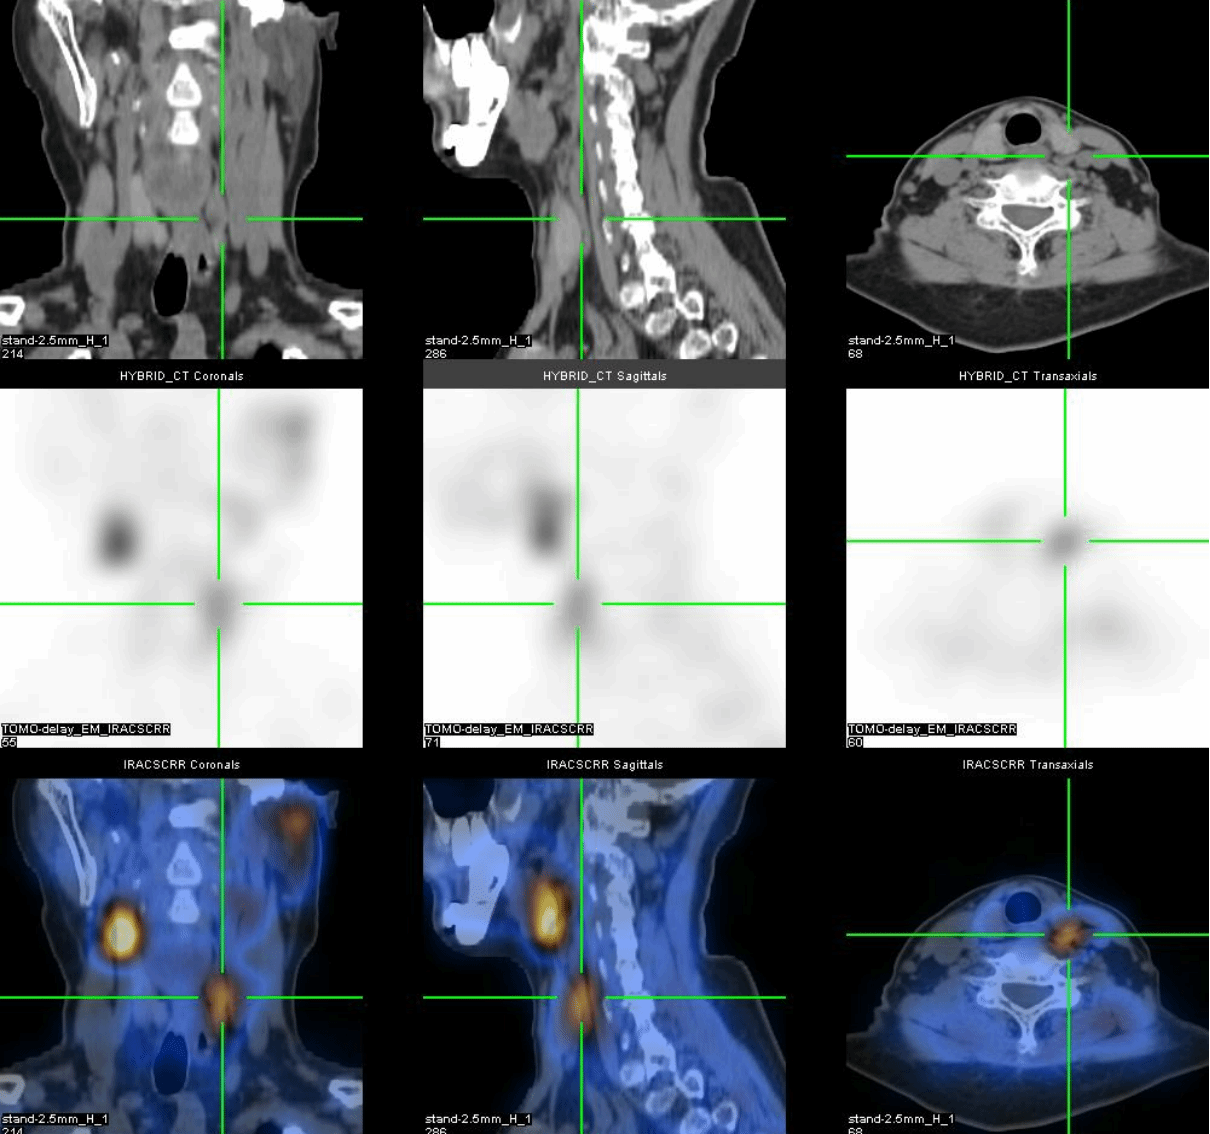

为了明确病变的位置,段阿姨又进行了核医学科的甲状旁腺显像(图5):

左侧甲状旁腺区显像剂浓聚较对侧稍增强,消退缓慢,提示可能为左侧甲状旁腺病变。

进一步的SPECT/CT断层融合显像(图6)显示,左上甲状旁腺形态增大,呈长条形,大小约1.3cm×0.6cm×4.5cm,并伴显像剂异常浓聚,考虑为功能亢进的甲状旁腺病变,首先考虑腺瘤。

后来段阿姨进行了手术治疗,病理为甲状旁腺腺瘤,术后段阿姨的血清钙恢复正常,PTH降低。